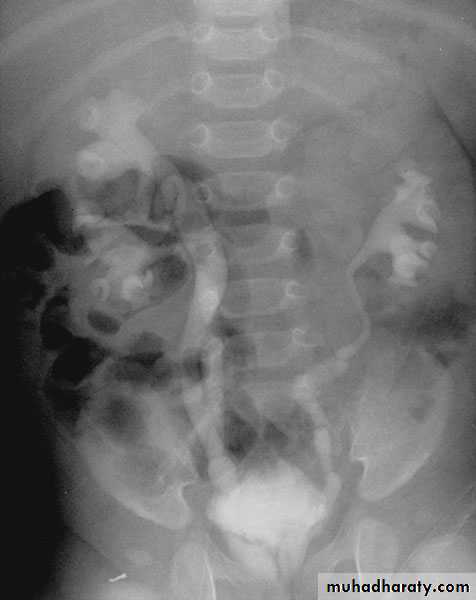

Ureteropelvic Junction (UPJ)(PUJ) Obstruction (stenosis)

Urology

The most common cause of significant dilation of the collecting system in the fetal kidney

Boys > Girls

Left-sided lesions predominate

15% bilateral

DIAGNOSIS

U/S: hydronephrosis

IVU: diagnostic , hydronephrosis with

fixed stenotic segment or complete

obstruction

CT scan: hydronephrosis that ends